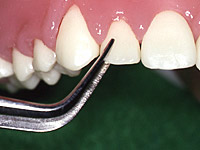

歯周病にかかった歯の周囲では、歯と歯肉の付着がはがれてポケット状の溝(歯周ポケット)が形成されます。ポケット深さの測定は、図のような目盛りの付いた先の丸いポケット探針を用いて行います。

歯周ポケットの深さを測定することにより、歯周病が根のどの位置まで進行しているかを知ることができます。一般的に4mm未満の歯周ポケットは正常値、それを超えるものを要注意として記録します。また炎症を起こした歯肉は出血しやすくなっているため、ポケット測定時の出血は歯肉の炎症の証拠として記録します。